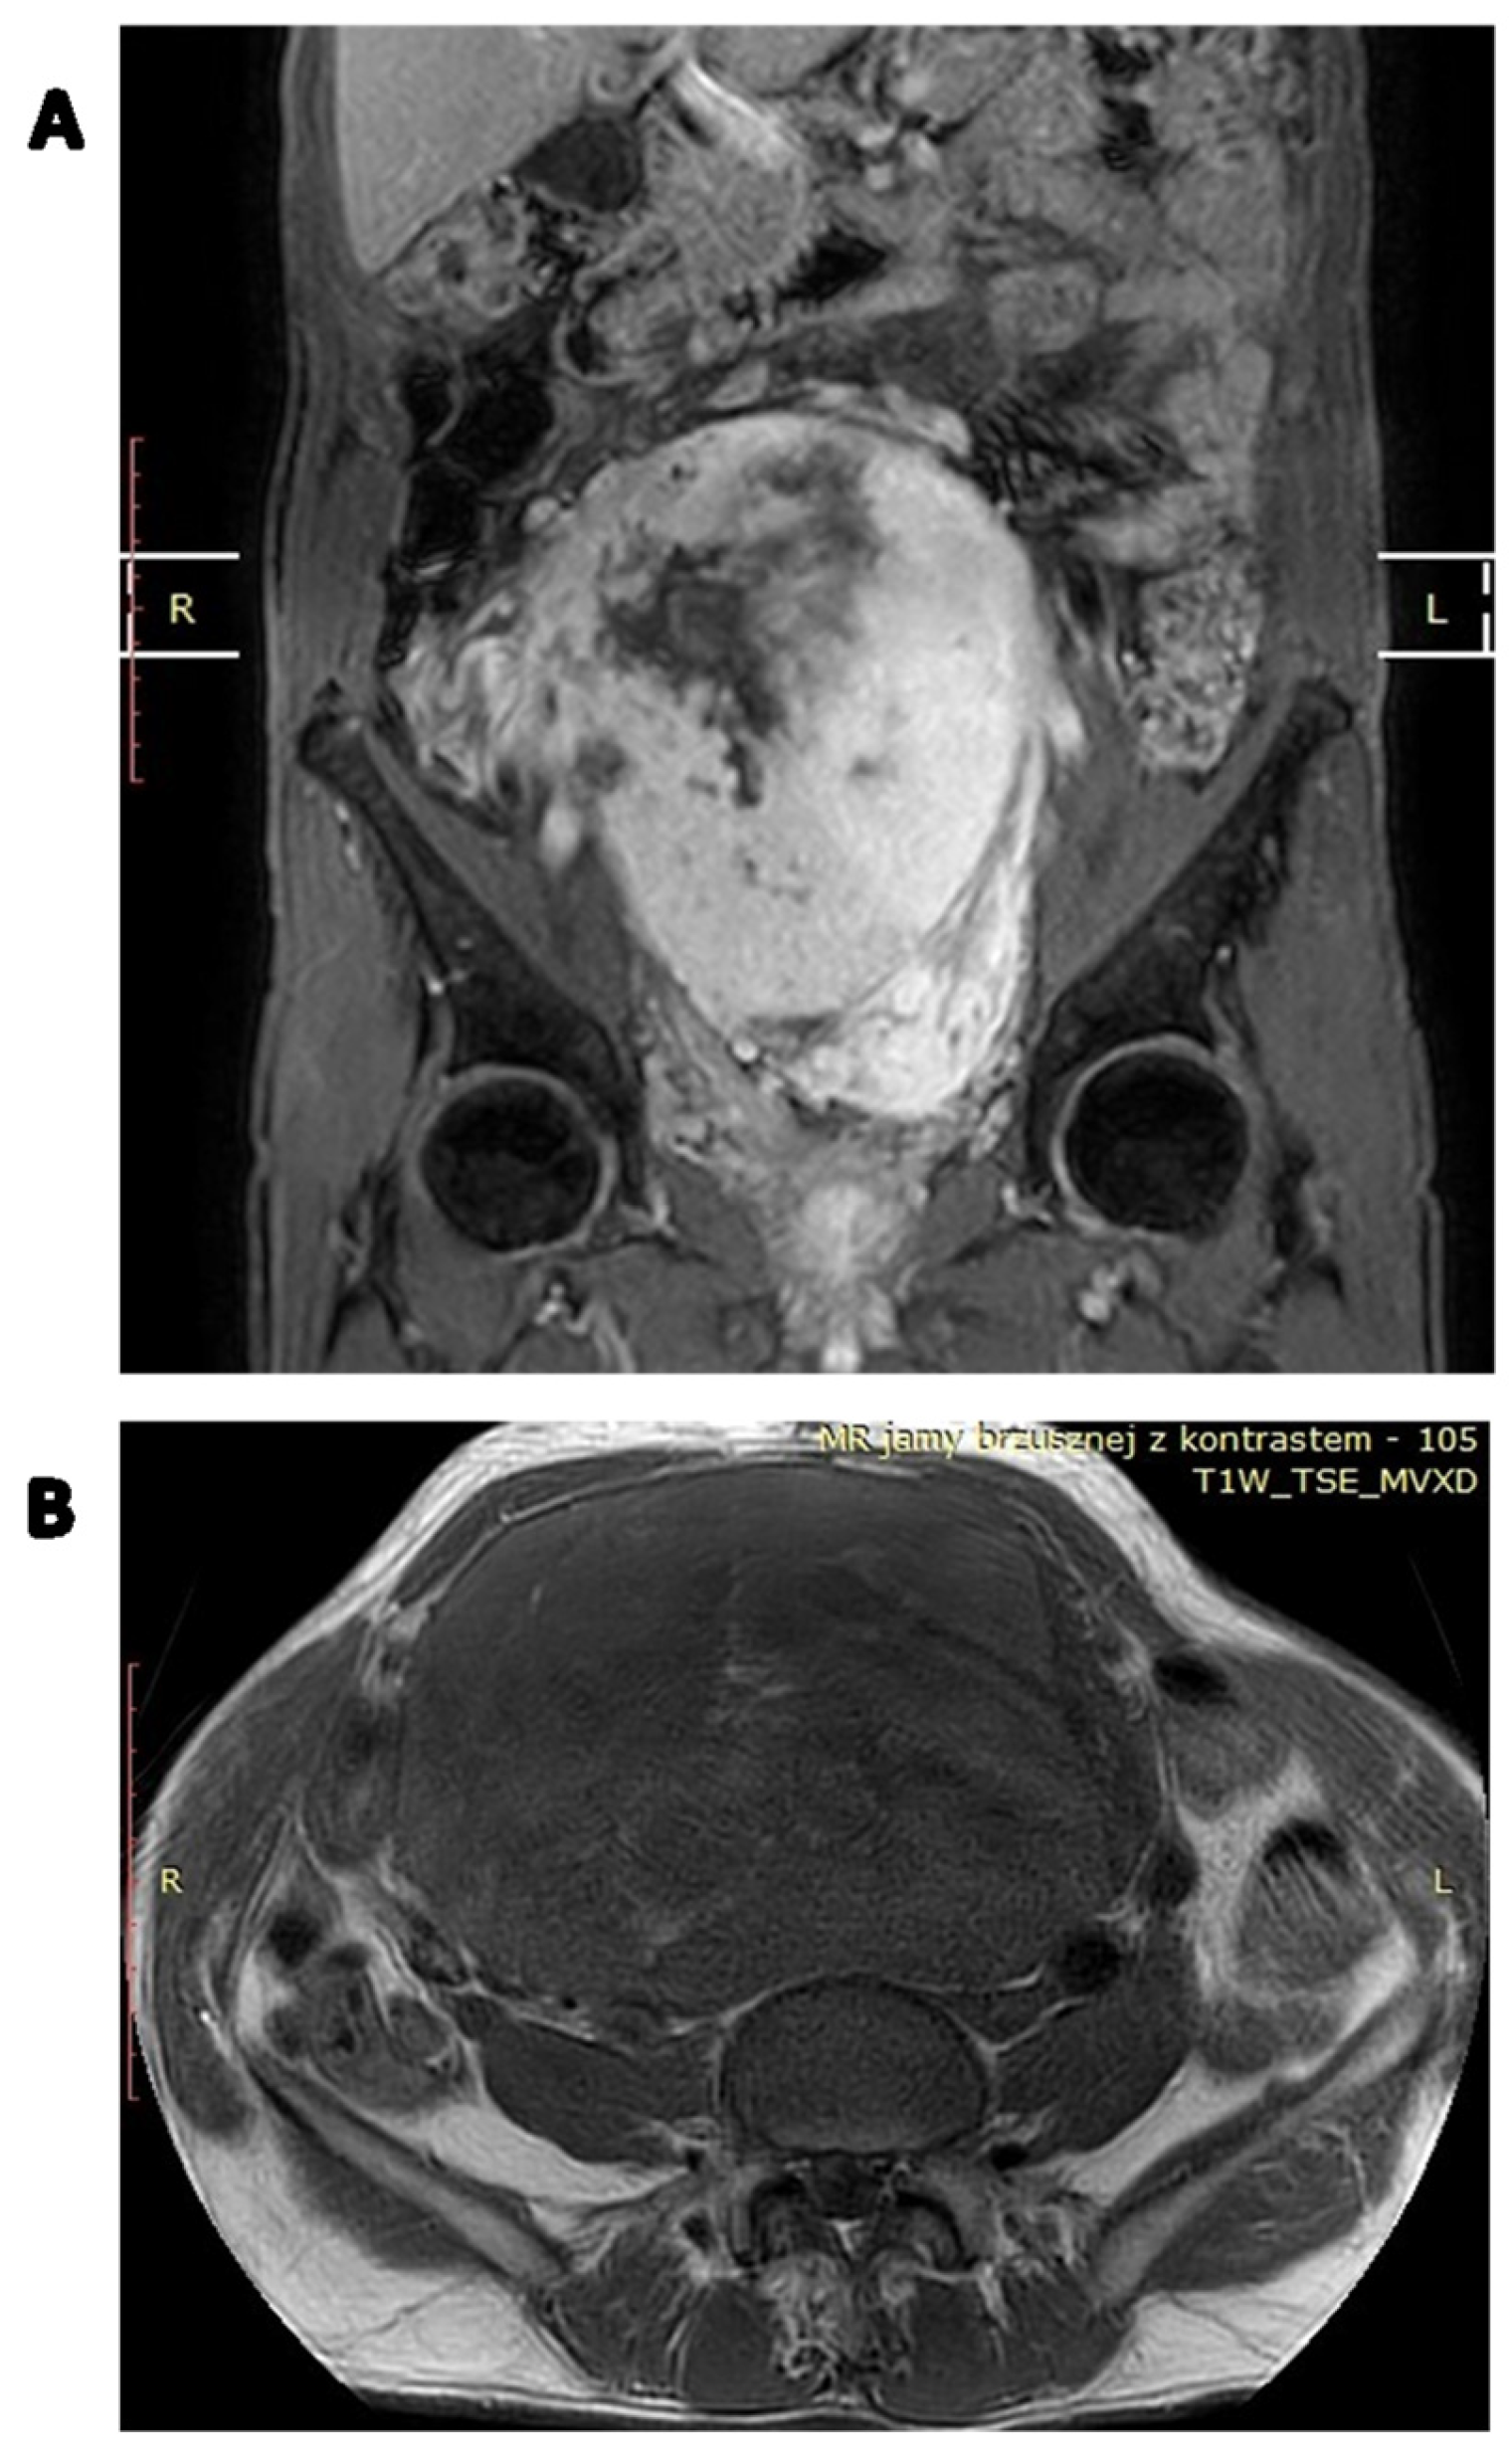

4. Diagnosis

7.2. Perioperative Radiotherapy